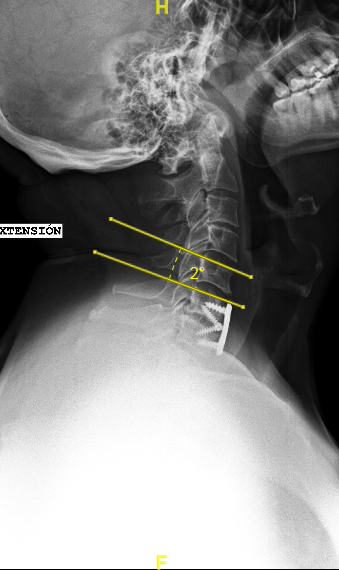

Las RX dinámicas reflejan la ausencia de fusión C6-C7